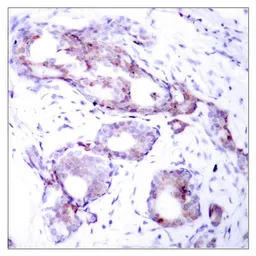

Anti-c-Myc (phospho Ser373) antibody used in IHC (Paraffin sections) (IHC-P). GTX50113

IHC-P analysis of human breast carcinoma tissue using GTX50113 c-Myc (phospho Ser373) antibody.